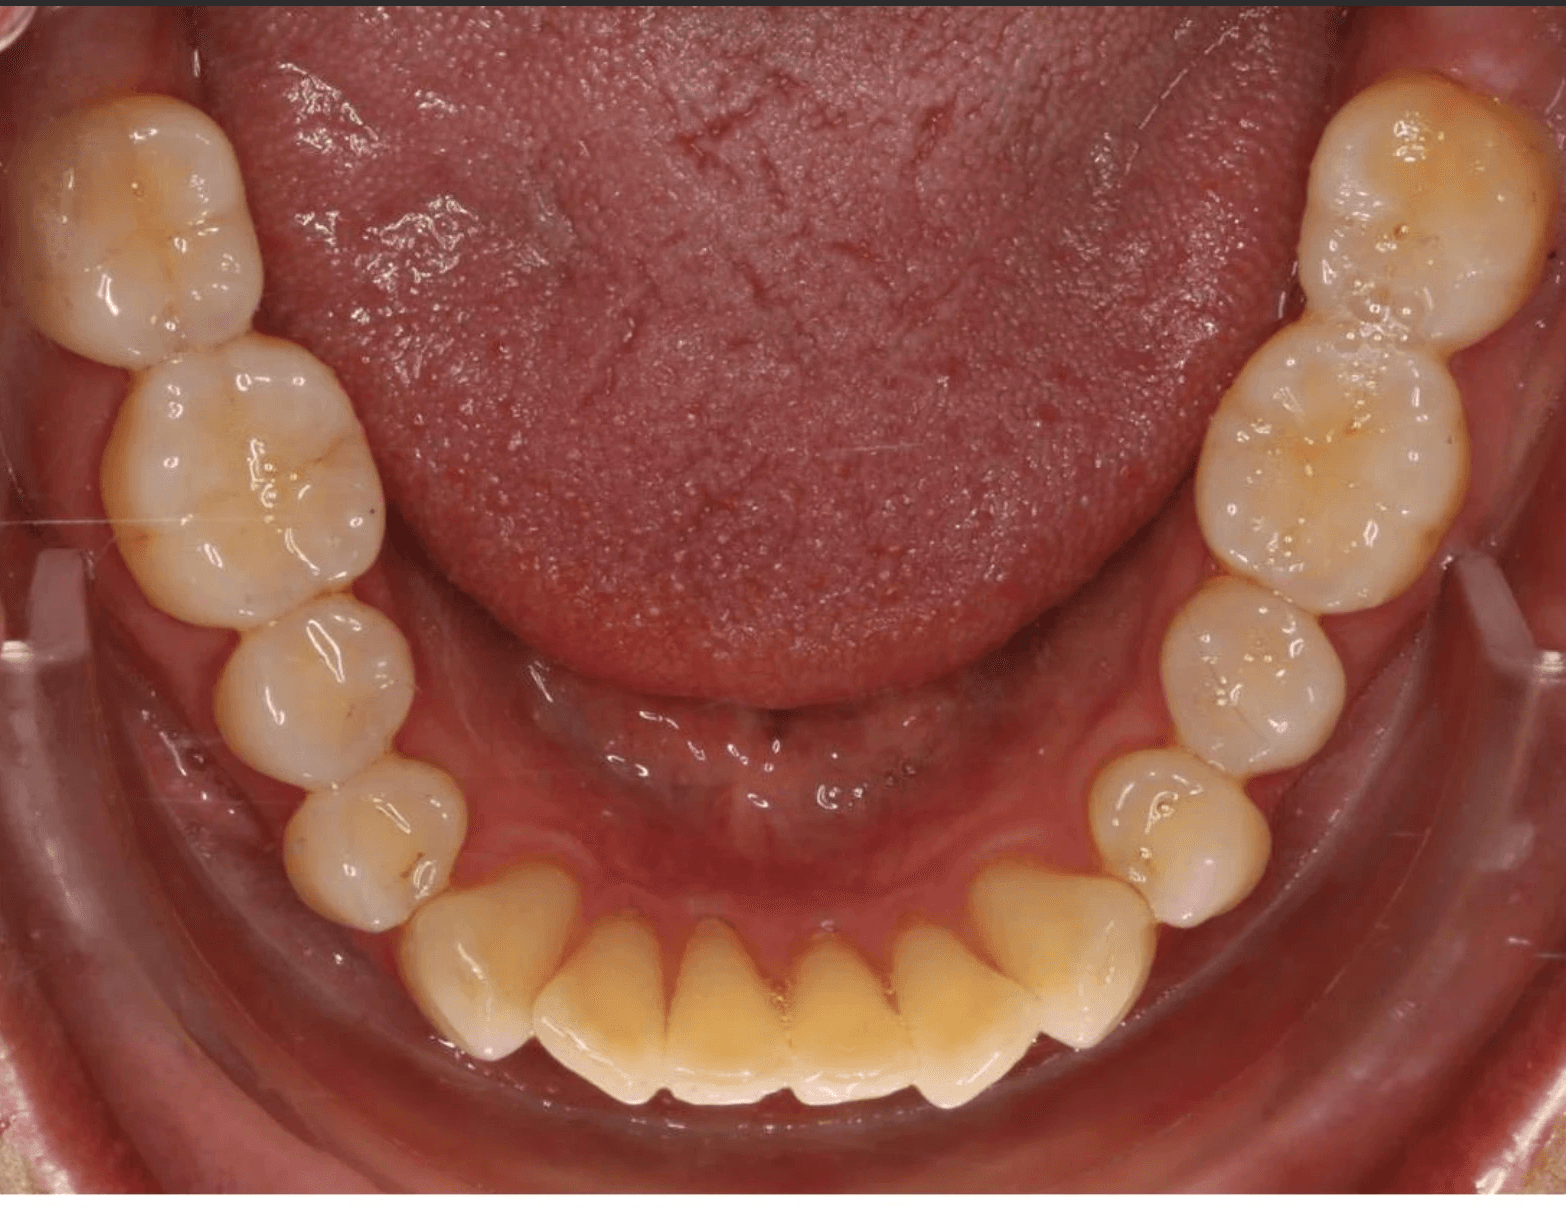

Diagnosis: A mix of crowding and mild spacing, moderate curve of Spee, black triangles, significant overjet, reverse smile display

Adjuncts: Bite ramps, attachments, IPR

Initial treatment

INTRAORAL